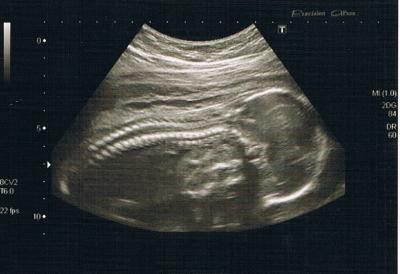

Mit der Kleinen alles super, optimale Werte. Laut Hebi (die arbeitet bei meiner FÄ) habe ich aber einen schlanken Bauch , Gebärmutter schon über dem Nabel, wie eig in der 24. SSW. Herzchen abhören möchte meine Kleine nicht, hat gegen das Abhörgerät getreten. Dann war sie beleidigt, hat ihr Gesicht in die Gebärmutterwand vergraben, sich nicht mehr gezeigt und bis eben keinen merkbaren Tritt mehr von sich gegeben . Jetzt schon eine kleine Zicke. Lt. FÄ hat sie lange Beine, weil die Oberschenkelknochen lang seien. Also entweder Model oder Baskettballspieler, meine Lieben. Größe kann ich nur schätzen durch die Rechnung FL x 7= Das wären dann 29,4 cm. Erscheint mir zu groß. Aber sie hat ja gesagt, die Knochen seien groß. Hat gesagt, dass es aussieht nach einem Mädchen. Sollen Schamlippen zu sehen gewesen seien. Aber sicher wirkte sie nicht. Es bleibt also bei meinen 90 % aus der Klinik. Anbei noch ein Foto von meinem kleinen Kung Fu-Panda, der momentan schläft. Nächster Termin am 04.07.2011.

Bild zu VU + Foto - Forum für Oktober - Mamis